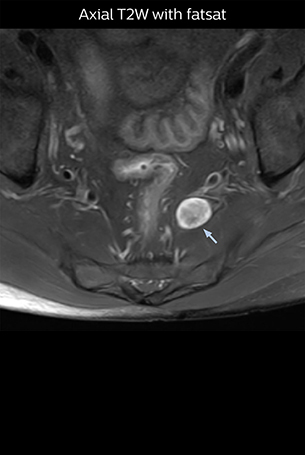

“The intra-luminal signal of veins, especially around the intervertebral space, can be suppressed well with NerveVIEW. As a result, we can easily observe the detailed nerve structure around the posterior ganglion,” he says. “This is why we use 3D NerveVIEW for intraforaminal stenosis and extraforaminal stenosis/herniation (lateral disc herniation). On the other hand, if herniation is suspected to exist inside the dorsal root ganglion (DRG), balanced TFE or ProSet-FFE is applied. NerveVIEW is not suitable for evaluating the median type of herniation.” The SE-EPI DWI-based method for MR neurography works well for large FOV exams like whole-body MRI, but focal examination of nerves is often limited by the attainable spatial resolution (both inplane and slice direction) and geometric distortion. “3D NerveVIEW achieves higher in-plane resolution – close to our other routine spine sequences – and the source images can be used instead of adding a fat-suppressed T2-weighted sequence,” Tanji says.

According to Tanji, methods such as ProSet FFE, STIR or 3D VISTA are anatomically nonselective because background signals, for instance from blood vessels, often interfere with nerves, which hampers evaluation of details, especially at the peripheral side of the nerves.

Implementing NerveVIEW without lengthening exam time “The source images of NerveVIEW exhibit a contrast similar to STIR or fat-suppressed T2-weighted images. So, in our neurography exams we are replacing the 2D T2-weighted coronal sequence with 3D NerveVIEW. With this, we add a lot of useful information without adding scan time. This is important for patients with severe lower extremity symptoms, as they often find it difficult to maintain still during the whole MRI examination, so the exam should be as short as possible.” “We have currently implemented 3D NerveVIEW on our Achieva 3.0T dStream MRI system only. Because the 3D NerveVIEW method is based on a background signal suppression technique, we decided to use the high SNR of our 3.0T MRI system for obtaining the best possible visualization of peripheral nerves,” says Tanji. “Where NerveVIEW of the lumbar plexus is currently used as a subroutine scan for patients with strong lower limb symptoms, its use for visualization of the brachial plexus, is currently limited to special cases such as schwannomas and neuritis, usually only 1 or 2 cases per month.”